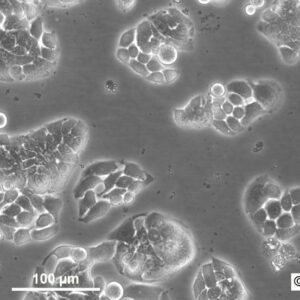

Morphology: Epithelial-like

Growth Properties: Adherent

Description: HuH7 was established in 1982 by Nakabayashi et al. from a 57-year-old Japanese male with well differentiated hepatocellular carcinoma.